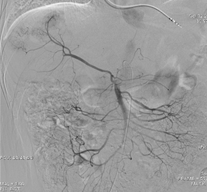

DSA造影示肝右叶多发病灶染色

3D MIP重建选择最佳的治疗角度,栓塞完成后再次造影示瘤体栓塞完全,非减影图像下示碘油存积良好